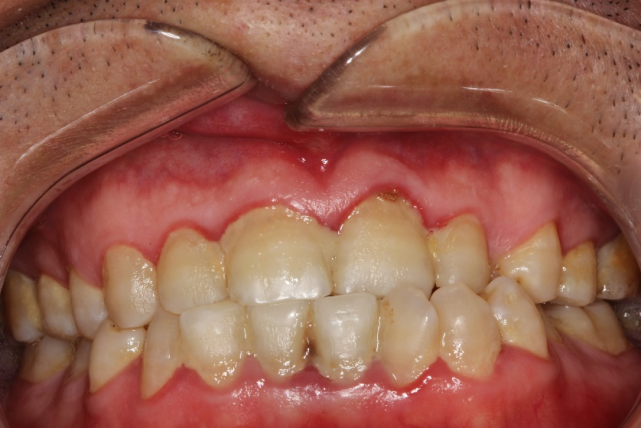

急 ! 这是牙龈线性红斑么? 还是一般的牙龈红肿?

(牙龈线性红斑多为艾滋病患者得!)严重的话会发展成坏死性牙周炎!

特征性的表现是沿着牙龈边缘分布的界限清晰的火红色改变,看起来很像

【专题讨论】大家看看这个患者是否有艾滋病 [病例帖]